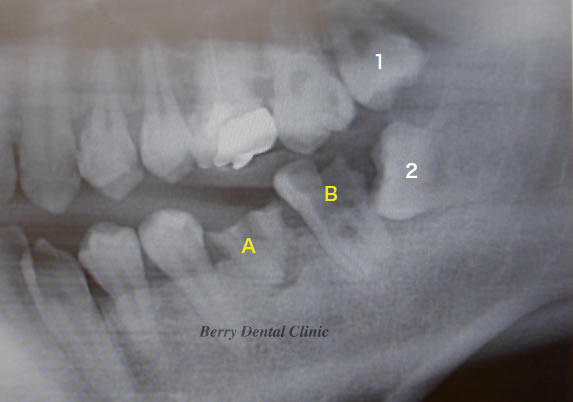

下の画像は実際に親知らずを利用した症例です。

上の画像のようにAとBの歯を残念ながら抜歯をしなければいけなくなりました。

最初にAを抜歯して1の親知らずを移植しました。

次に安定した後、Bの歯を抜歯して2の親知らずを移植しました。